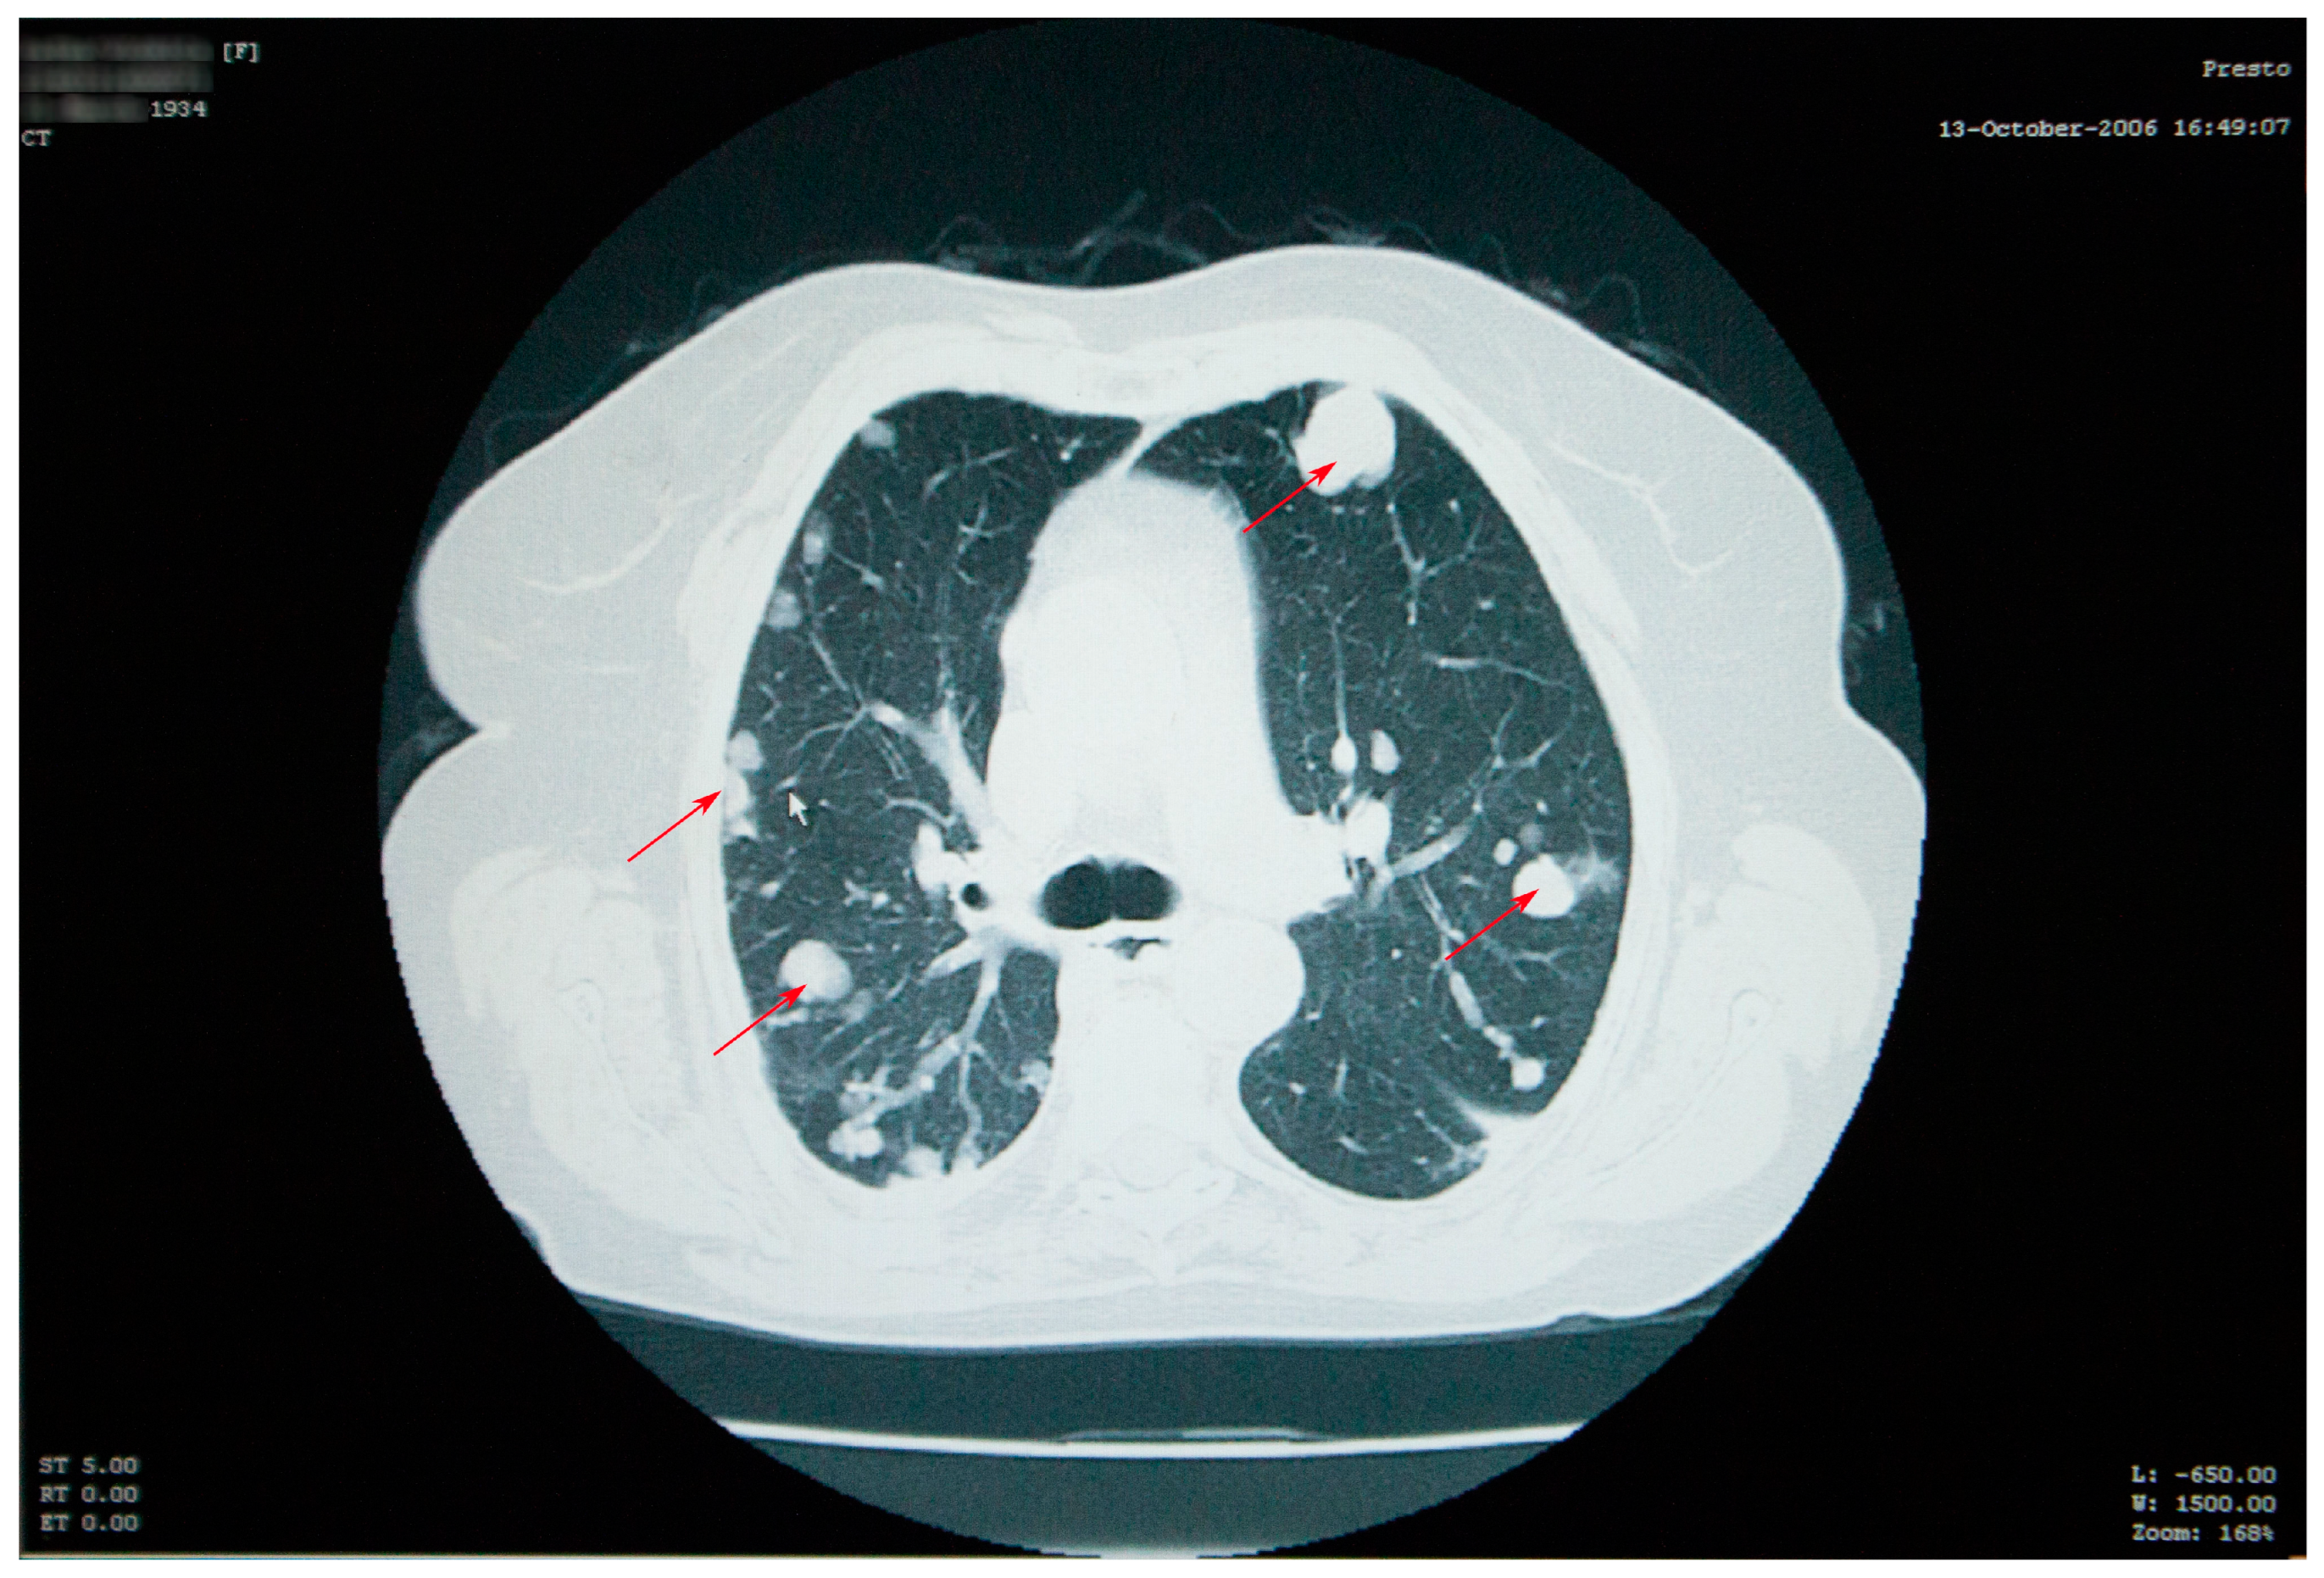

Abdominal imaging revealed multiple cysts, with lots of septa, confluent in the right kidney space, invading the retroperitoneal area down into the right pelvic region, situated between the aorta and the vena cava. Similar types of damage were visible in the sixth right liver segment, as well as the right iliac fossa, and the right paravertebral region (Figure 3).

The right kidney could not be visualized. The psoas muscle, along with the spaces between intestinal loops, had been infiltrated by the same sort of septate cystic masses. A somewhat larger mass, with a size of 45/33 mm, was observed adjacent to the bowel on the right side. The specific serology was intensely positive.

Figure 3. Abdominal CT scan showing multiple cysts, confluent in the right kidney space (red diamond), invading the retroperitoneal area, in the sixth right liver segment (star) and in the right iliac fossa and right paravertebral area (arrow).